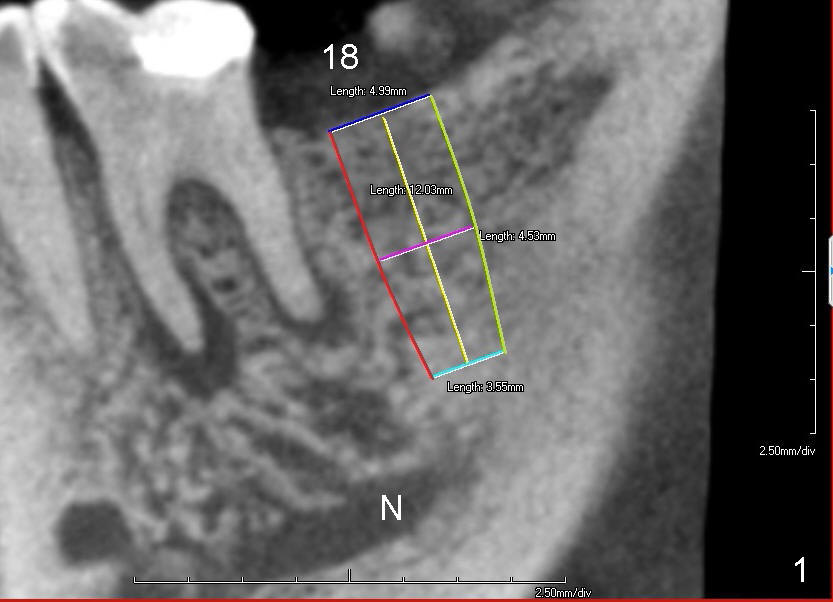

Traditionally, implant placement concentrates upon not touching the neighboring root or the nerve (Fig.1 (CT sagittal section), 2 (coronal) N) and inside the buccal and lingual plates (Fig.2 B, L). The design does not consider opposing dentition.

Probably due to long standing edentulism, the buccal plate is atrophic. In order for the future crown (mainly its buccal cusp) to occlude with the lingual cusp (Fig.4 L, functional cusp) of the upper 2nd molar, the coronal end of the bone-level implant should be more buccal than the traditional one (Fig.2), whereas the apical end more lingual. But not too much! The lingual plate should be protected. Place a finger in the submandibular fossa (SF) while making osteotomy.

Root canal therapy has been done for the tooth #19. Before surgery, take a PA using the existing layout to confirm that the apical radiolucency has been reduced or disappeared. After finishing 2 mm pilot drilling at the depth 8 mm, insert a paralleling pin and check the trajectory against the upper opposing tooth. Make necessary adjustment with Linderman bur. Then take PA to check mesiodistal trajectory and proximity to the nerve. Deepen osteotomy to 12 mm (deeper than 11 mm mark). Use reamers for further osteotomy. The autogenous bone will be saved and placed most likely in the buccal aspect when the buccal threads are exposed (Fig.4: red circle). Use collagen dressing (apron-shaped with a hole in the middle, buccal portion wider). Use a 5.2 (or 6.2 mm) healing abutment to hold the dressing in place. From Fig.4, can you guess what length and cuff should be chosen? How is the result?